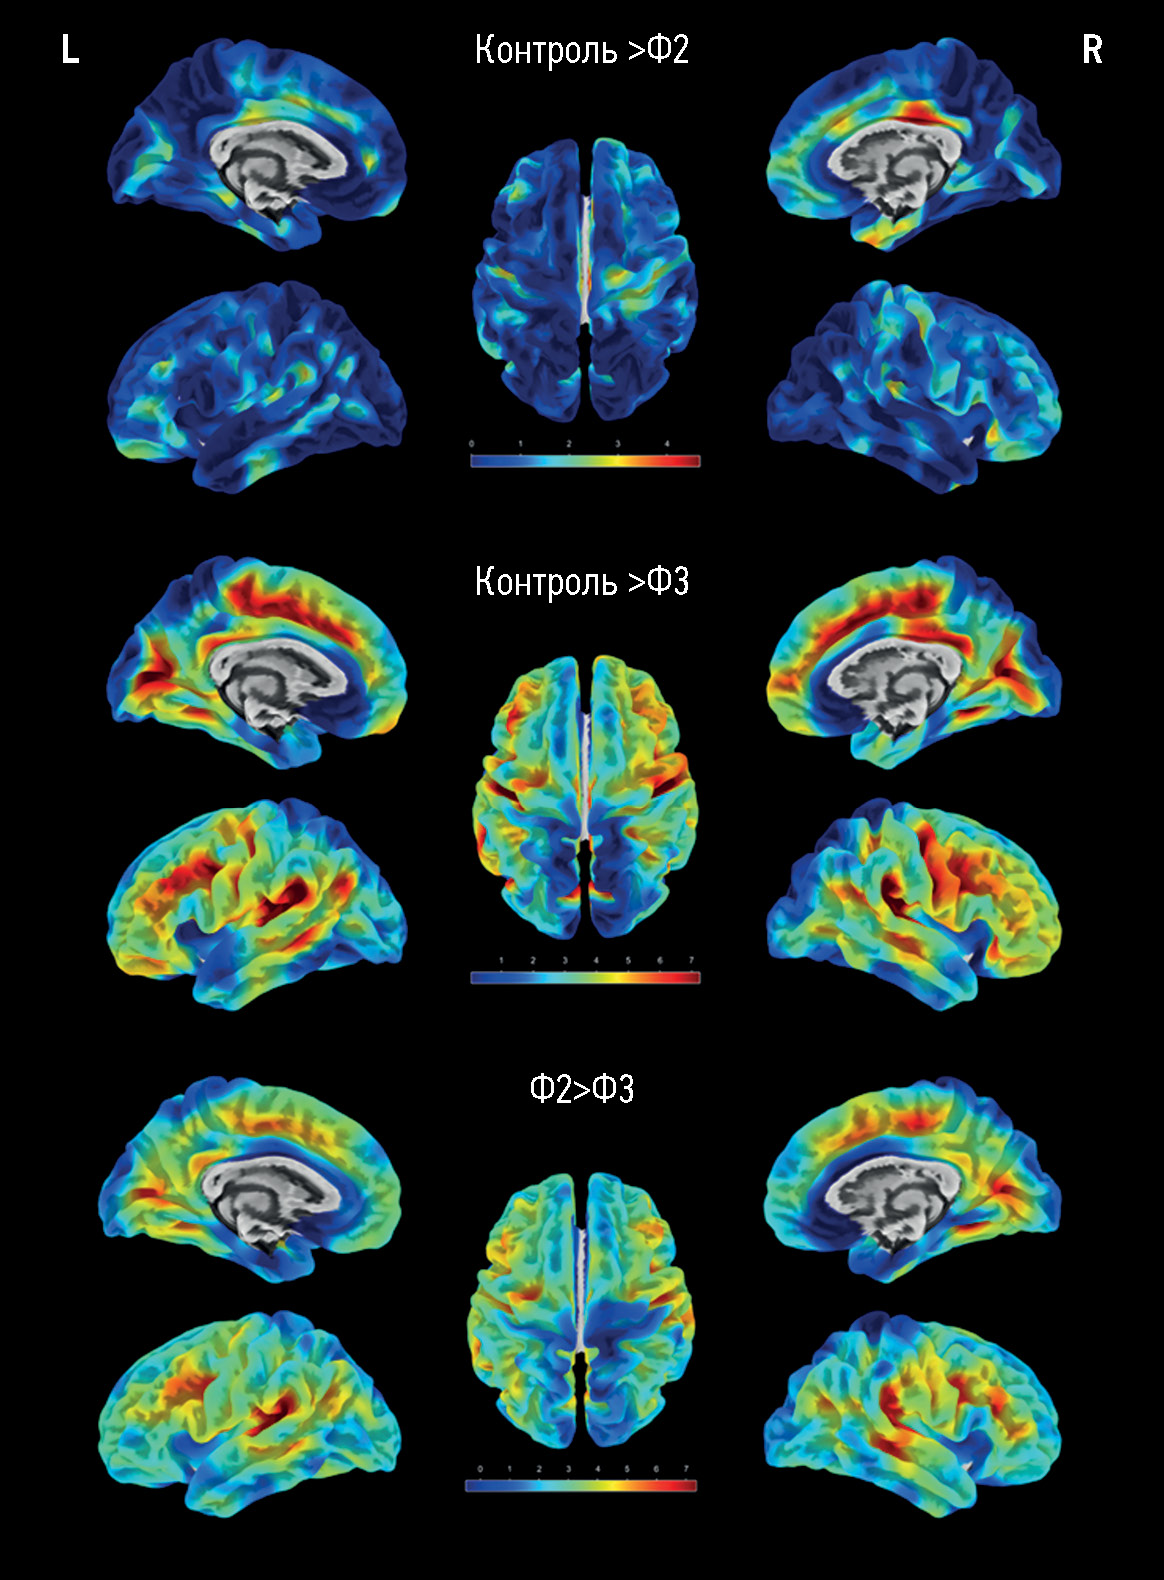

Результаты. В основную группу вошли 173 пациента с церебральной микроангиопатией, в группу контроля ― 47 здоровых добровольцев. По мере нарастания выраженности структурных изменений головного мозга и тяжести когнитивных расстройств отмечалось достоверное (p <0,05) уменьшение толщины коры отдельных регионов по схожему паттерну, а именно: поясных извилин, преимущественно задних их отделов; медиальных и средних отделов лобных долей; различных участков коры островка; височно-теменных областей (особенно надкраевых извилин). Объём самогó головного мозга (общий объём, объём серого и белого вещества) при церебральной микроангиопатии имел значимые различия только с контролем, но не между группами пациентов с разной тяжестью когнитивных расстройств. Объём гиперинтенсивного белого вещества значимо различался между группами с деменцией и умеренными когнитивными расстройствами, деменцией и субъективными когнитивными расстройствами (p <0,0001).

Заключение. Полученные в ходе исследования данные подтверждают вторичный/смешанный характер атрофии при церебральной микроангиопатии. Большое разнообразие регионов со значимым истончением коры ограничивает уточнение прогрессирования когнитивных расстройств при церебральной микроангиопатии по их атрофии. Это позволяет использовать количественное измерение коры только как вспомогательный метод при оценке прогнозирования течения церебральной микроангиопатии.